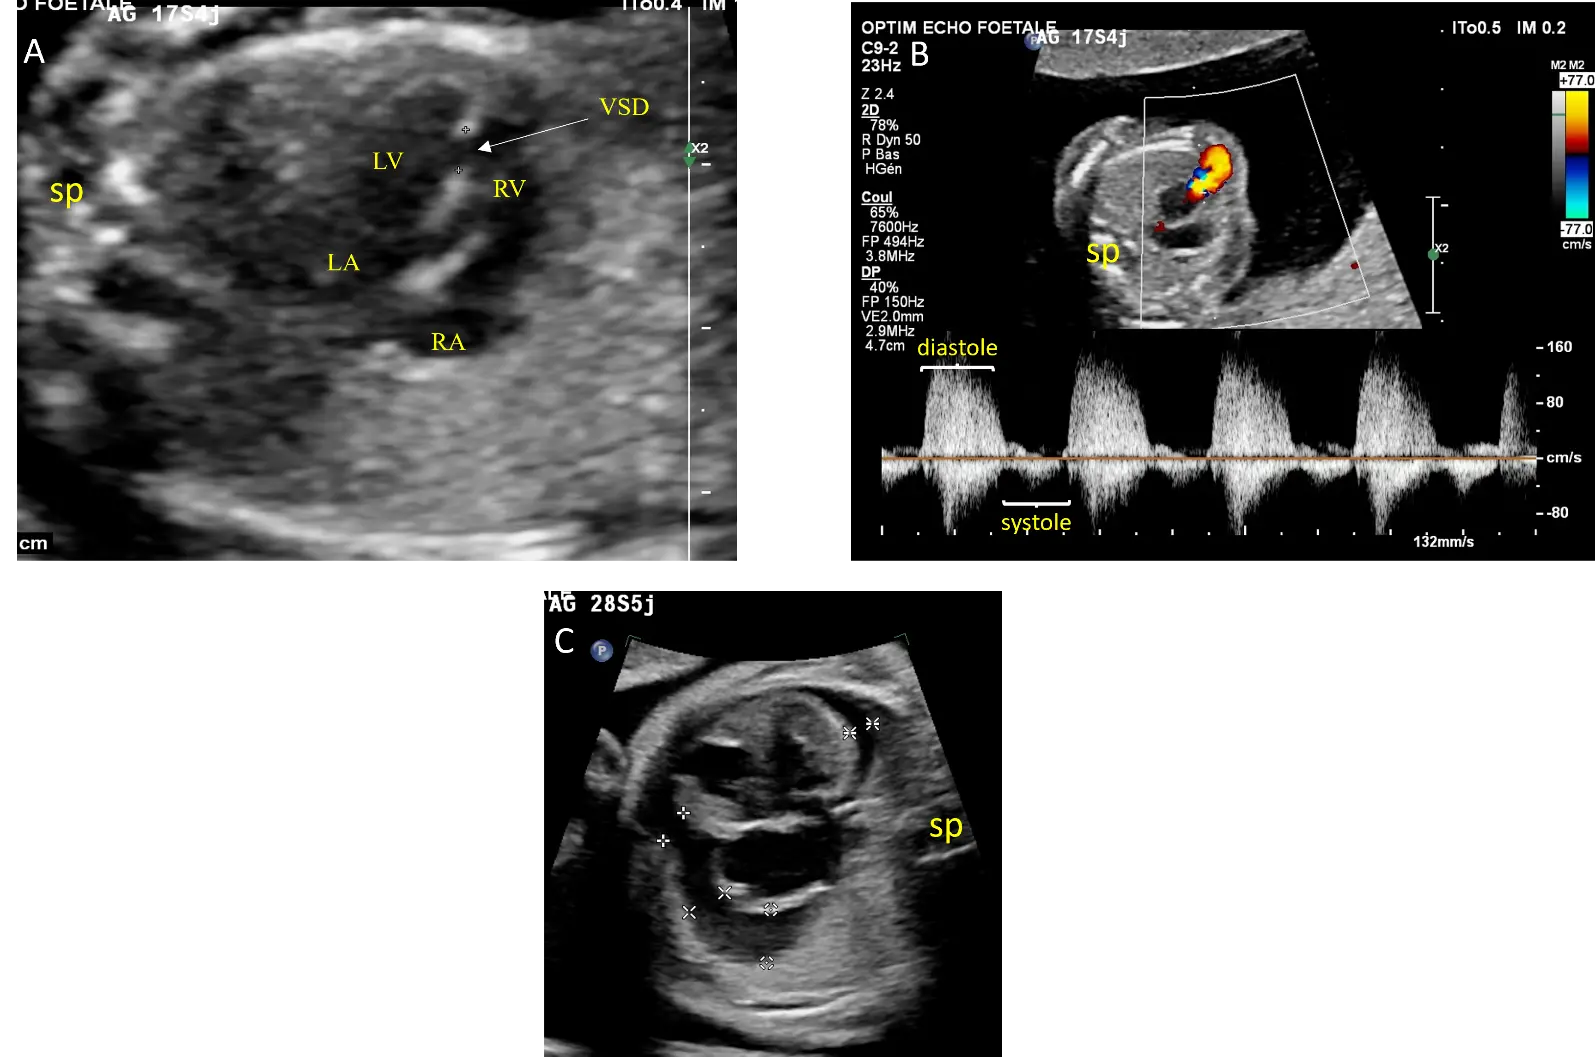

Fetal echocardiography revealed an absent pulmonary valve with to-and-fro flow across the pulmonary orifice and the ductus arteriosus. A muscular VSD was present, but there was no Fallot-type VSD. The pulmonary trunk was significantly dilated, while the pulmonary branches remained unaffected. There was no tricuspid regurgitation. The aortic arch was oriented to the left. The mother declined amniocentesis.

Subsequent serial fetal ultrasounds demonstrated cardiomegaly and pericardial effusion at 28 weeks of gestation (Figure 2). At 34 weeks of gestation, fetal intra uterine demise was found. The parents declined an autopsy. Karyotype analysis of the placenta did not reveal genetic anomalies.

Figure 2. Echocardiographic views from case #2: Four chamber view showing a muscular ventricular septal defect (VSD) delimited by calipers and balanced ventricular and atrial cavities without cardiomegaly at 17 weeks of gestation (A). Doppler interrogation of the pulmonary annulus showing pulmonary insufficiency (B). At 28 weeks of gestation, there is pericardial effusion marked by calipers (C). LA: Left atrium, LV: left ventricle, RA: right atrium, RV: right ventricle, sp: spine.